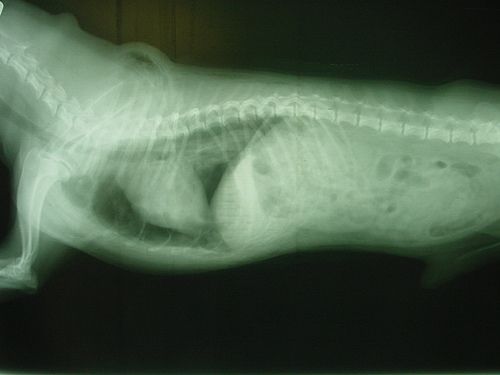

#betegség#kutya#mellkas#mellvízkórA mellkas egyéb megbetegedései@jszakai•2011. aug. 16.•1 perc olvasás